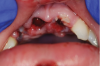

Orofacial injuries from ENDS explosions have been documented with low incidence.37 These incidents tend to occur due to excessive heating of the unit's internal lithium-ion battery. Injuries can include tooth fractures, dentoalveolar fractures, hematoma formation, traumatic ulceration, burns, and palatal perforation (Figure 4 through Figure 7). Soft-tissue damage may require cosmetic and functional surgical reconstruction.

Fig 4. Oral injuries after e-cig explosion. Fig 4: Laceration of the lower lip vermillion with ecchymosis; Fig 5: Multiple lacerations with surrounding erythema on the upper labial mucosa; Fig 6: Hematoma of the lower labial mucosa with small midline ulceration; Fig 7: Resultant dental injuries included complete intrusion of tooth No. 7, avulsion of tooth No. 8, fracture of tooth No. 9 to the gingival margin, and incisal fracture of tooth No. 10. (Reprinted with permission from Journal of Oral and Maxillofacial Surgery.37 Copyright 2016, Elsevier)

Fig 5. Oral injuries after e-cig explosion. Fig 4: Laceration of the lower lip vermillion with ecchymosis; Fig 5: Multiple lacerations with surrounding erythema on the upper labial mucosa; Fig 6: Hematoma of the lower labial mucosa with small midline ulceration; Fig 7: Resultant dental injuries included complete intrusion of tooth No. 7, avulsion of tooth No. 8, fracture of tooth No. 9 to the gingival margin, and incisal fracture of tooth No. 10. (Reprinted with permission from Journal of Oral and Maxillofacial Surgery.37 Copyright 2016, Elsevier)

Fig 6. Oral injuries after e-cig explosion. Fig 4: Laceration of the lower lip vermillion with ecchymosis; Fig 5: Multiple lacerations with surrounding erythema on the upper labial mucosa; Fig 6: Hematoma of the lower labial mucosa with small midline ulceration; Fig 7: Resultant dental injuries included complete intrusion of tooth No. 7, avulsion of tooth No. 8, fracture of tooth No. 9 to the gingival margin, and incisal fracture of tooth No. 10. (Reprinted with permission from Journal of Oral and Maxillofacial Surgery.37 Copyright 2016, Elsevier)

Fig 7. Oral injuries after e-cig explosion. Fig 4: Laceration of the lower lip vermillion with ecchymosis; Fig 5: Multiple lacerations with surrounding erythema on the upper labial mucosa; Fig 6: Hematoma of the lower labial mucosa with small midline ulceration; Fig 7: Resultant dental injuries included complete intrusion of tooth No. 7, avulsion of tooth No. 8, fracture of tooth No. 9 to the gingival margin, and incisal fracture of tooth No. 10. (Reprinted with permission from Journal of Oral and Maxillofacial Surgery.37 Copyright 2016, Elsevier)